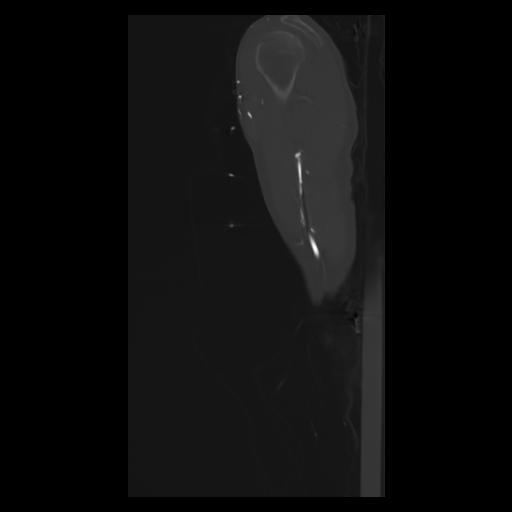

30 CUERPO,CE,Sagittal,3.000,CUERPO,Sagittal,